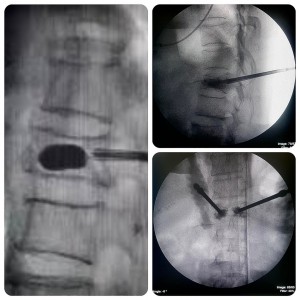

Sau 2 giờ phẫu thuật hiện tại bệnh nhân tỉnh táo đỡ đau vùng lưng. TS.BS Đoàn Anh Tuấn- PGĐ bệnh viện, phụ trách khoa chấn thương chỉnh hình thăm khám và chia sẻ sau phẫu thuật hiện tại bệnh nhân đã đỡ đau, kiểm tra trên C-arm thấy đốt sống sau bơm cement giãn tốt. Sau 6 giờ bệnh nhân có thể tự ngồi dậy, sau 1 ngày tập đi lại bình thường và sau 3 ngày bệnh nhân có thể xuất viện.

Bác sĩ thực hiện kĩ thuật bơm xi măng tạo hình đốt sống có bóng qua da